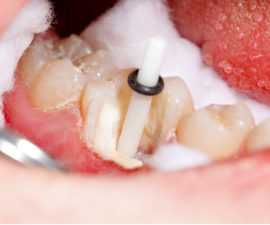

(Рис.1)

Изоляция зуба

До начала препарирования необходимо произвести тщательную изоляцию зуба с помощью коффердама. Можно воспользоваться флоссом, чтобы прижать коффердам ближе к десне, тем самым улучшая видимость краев зуба.

(Рис.2)

Обработка корневого канала

После прохождения инструментом Ларго №3, проводится обработка корневого канала ультразвуком, чтобы удалить весь цемент для улучшения адгезии.